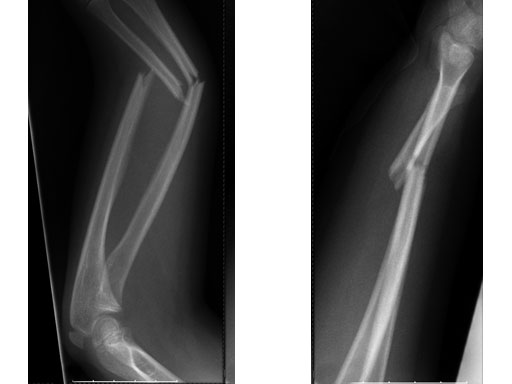

Case 2: Oblique forearm, shaft fracture (22D/5.1) with end caps, 11-year-old boy.

Case provided by Theddy Slongo, Bern, Switzerland